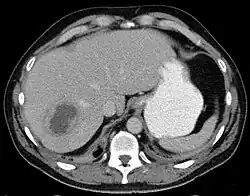

Liver abscess on axial CT image: a hypodense lesion in the liver with peripherally enhancement.